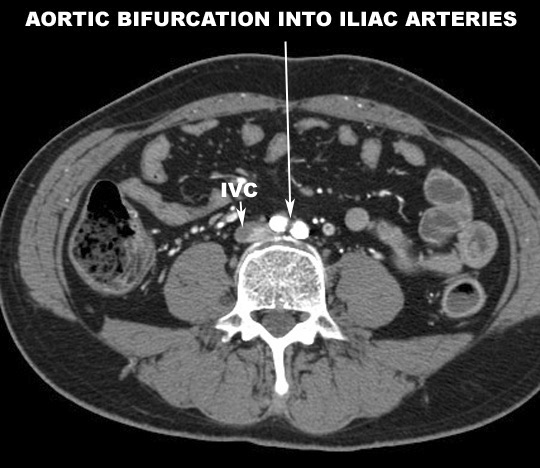

- Abdominal aorta ends by dividing at L4

into left and right common Iliac arteries

- About 4-5 cm in length

- Descends downward and outward toward the

edge of the pelvis.